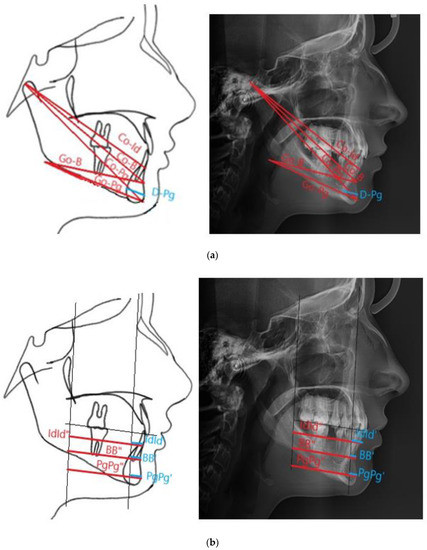

| BB′ | The distance between B and B′, in the authors’ study defined as the length of the anterior mandibular segment (the authors’ measurement) |

| BB″ | The distance between B and B″ |

| Co-B | The distance measured between Co and B points (the authors’ measurement) |

| Co-Id | The distance measured between Co and Id points (the authors’ measurement) |

| Co-Pg | The total mandibular length, the distance measured between Co and Pg points |

| D-Pg | The cross-sectional diameter of the mandibular symphysis, the distance between D and Pg points |

| Go-B | The length of the mandibular alveolar part, distances between Go and B points (the authors’ measurement) |

| Go-Pg | The mandibular body length, the distance between Go and Pg points |

| IdId′ | The distance between Id and Id′, defined as the anterior length of the mandibular alveolar part (the authors’ measurement) |

| IdId″ | The distance between Id and Id″ |

| PgPg′ | The distance between Pg and Pg′, defined as the length of the anterior mandibular part at the Pg height (the authors’ measurement) |

| PgPg″ | The distance between Pg and Pg″ |